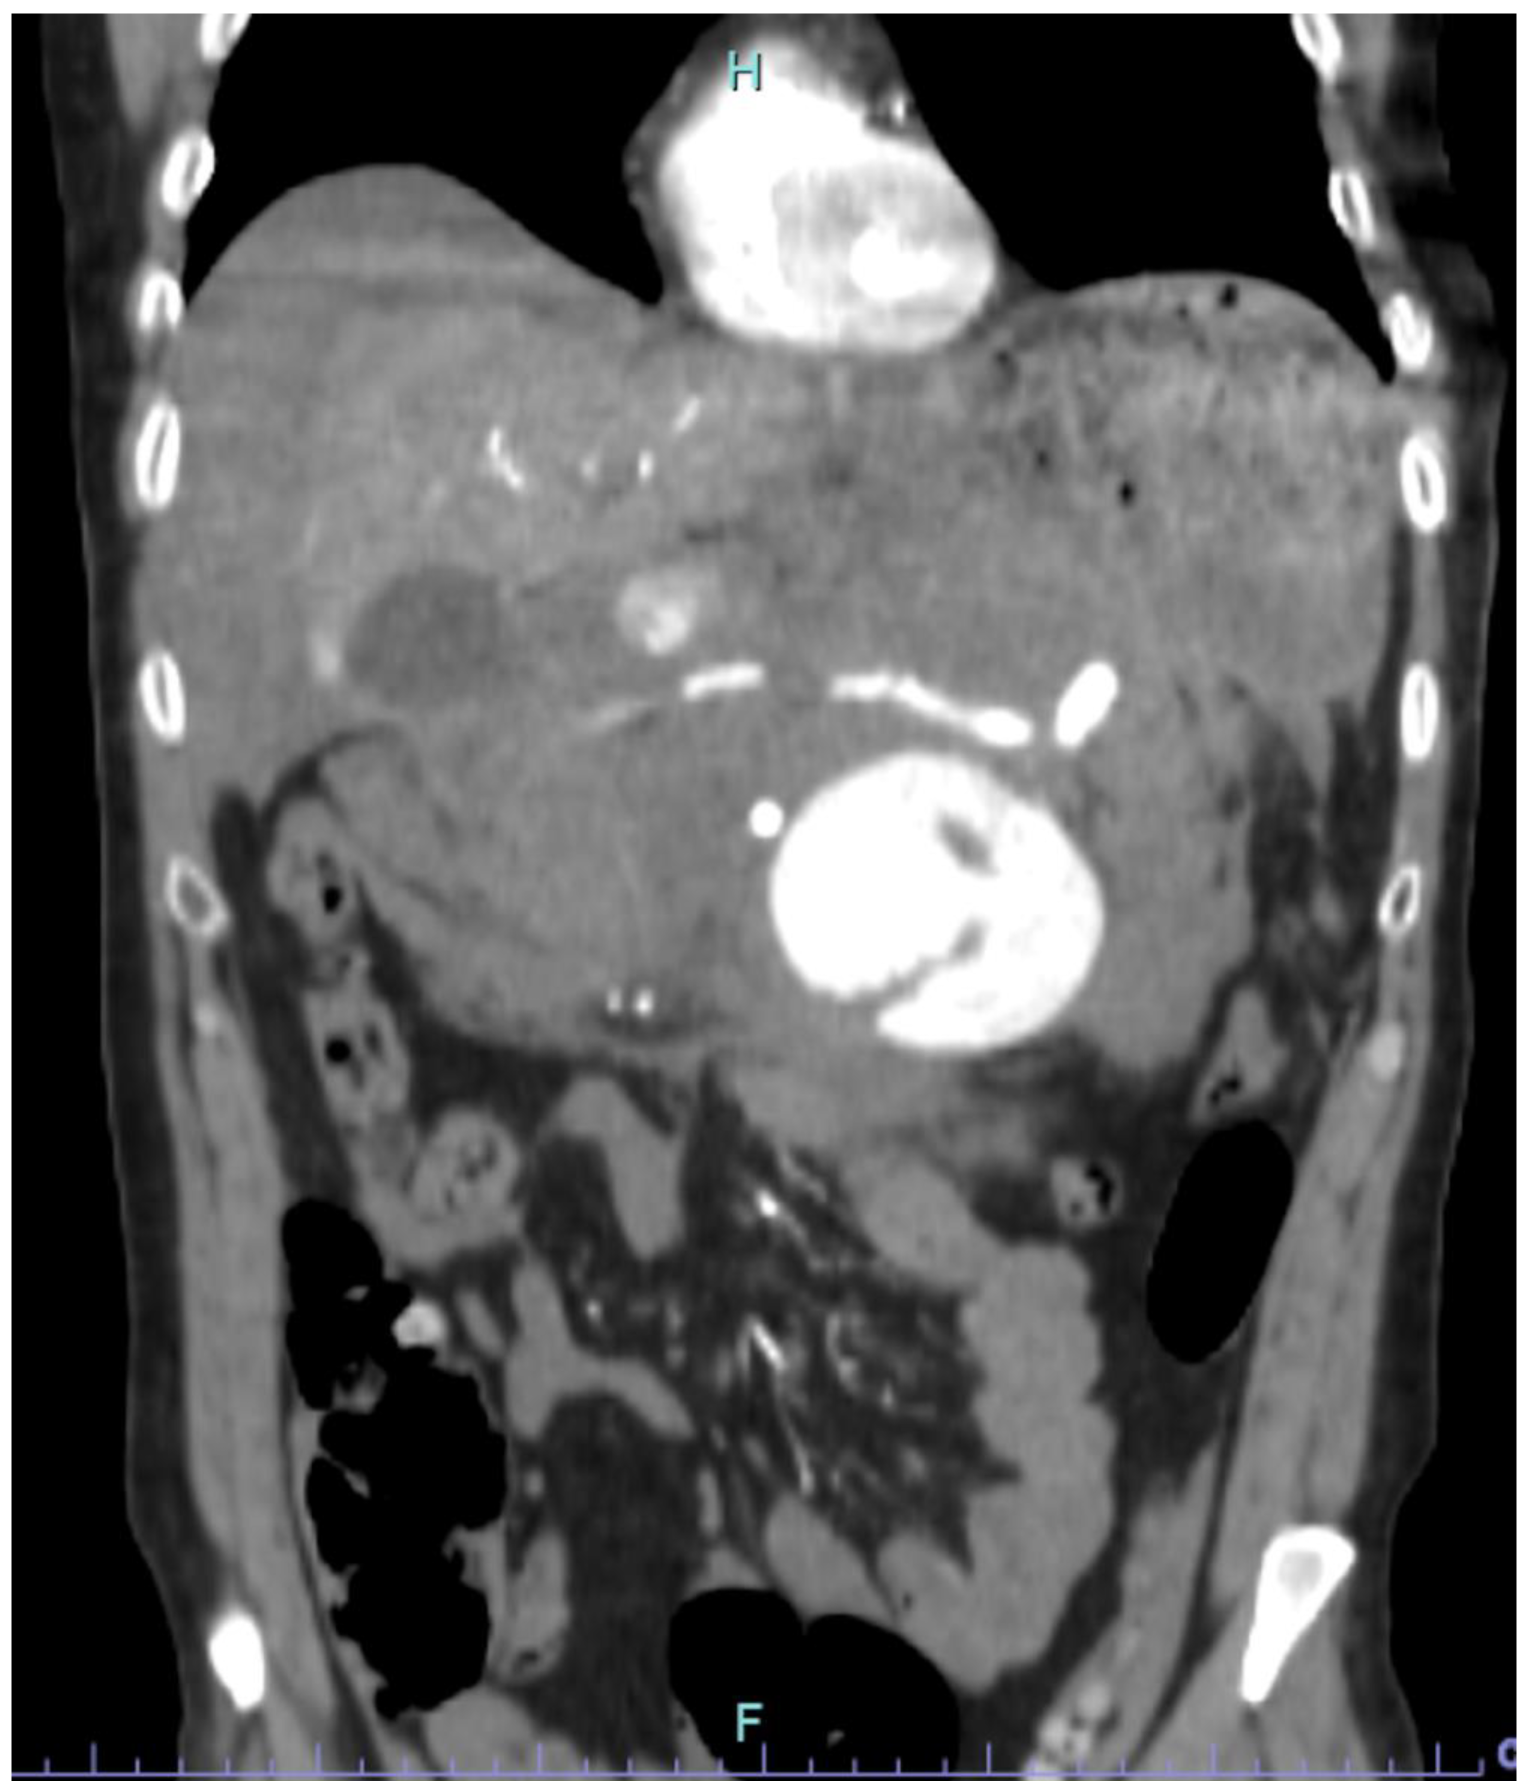

2.1. Case Report